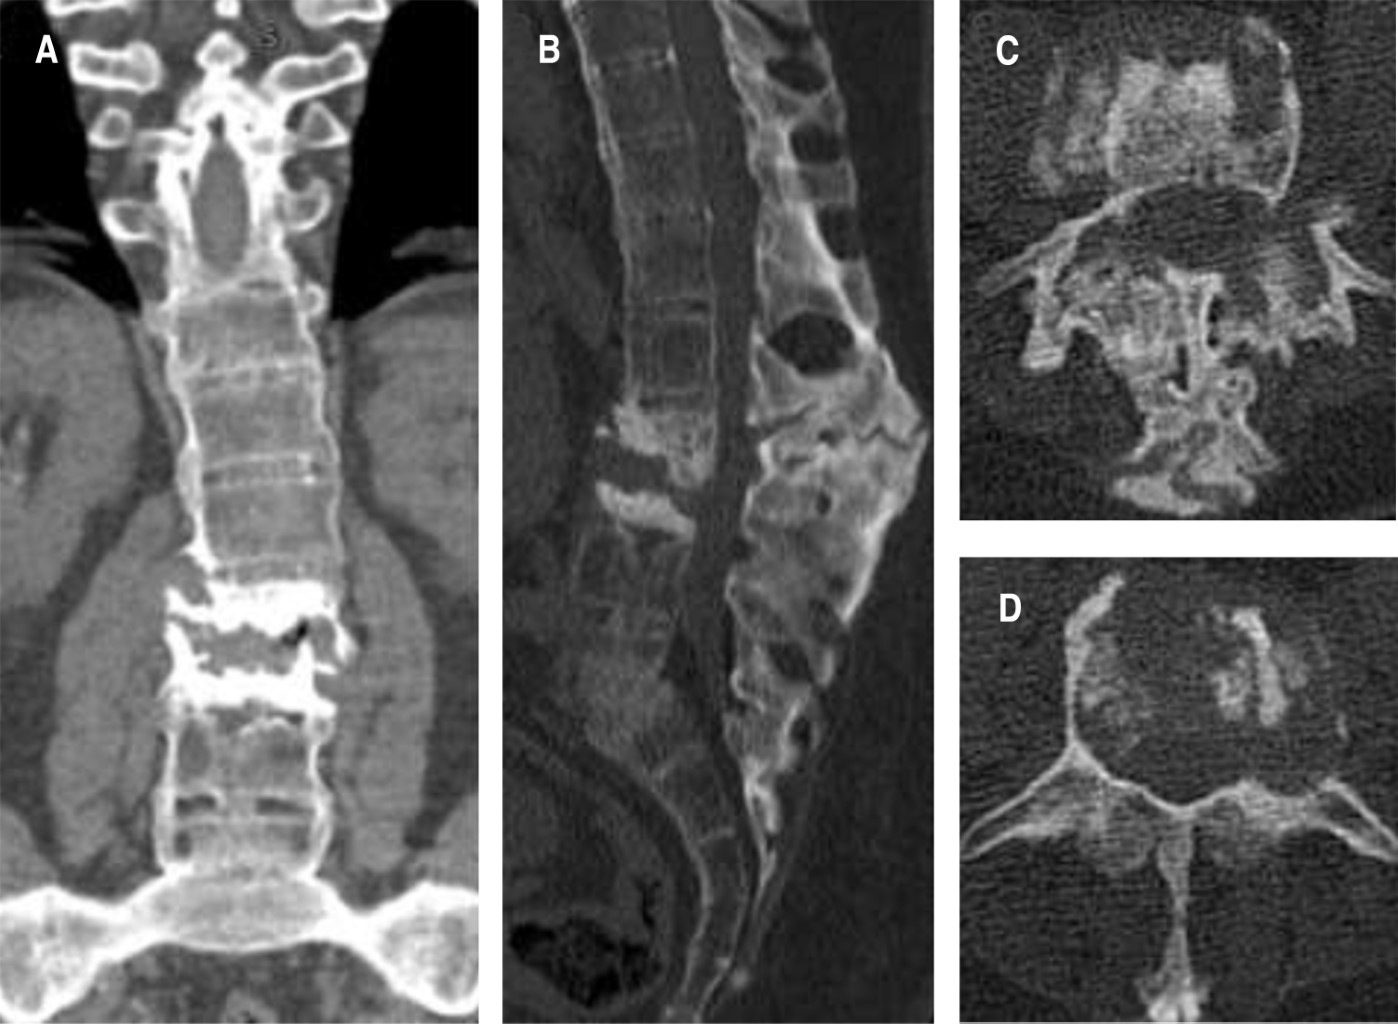

Masculino de 49 años, agricultor, obeso, tabaquismo por 30 años, dolor lumbar con aumento progresivo durante los últimos cinco años, intensidad 6/10 EVA, se intensifica con la movilización, se palpó lesión sólida en la línea media de la región torácica baja y lumbar alta, limitación de los movimientos del tronco, sin datos radiculares en extremidades inferiores (Figura 1). El paciente tenía estudio de HLA-B27 positivo. Estudios de imagen: columna toracolumbar en "caña de bambú", laterolistesis izquierda a nivel de fractura en cuerpo de L3, pseudoartrosis en L2-L3 y espondilolistesis L5-S1. (Figuras 2, 3 y 4).